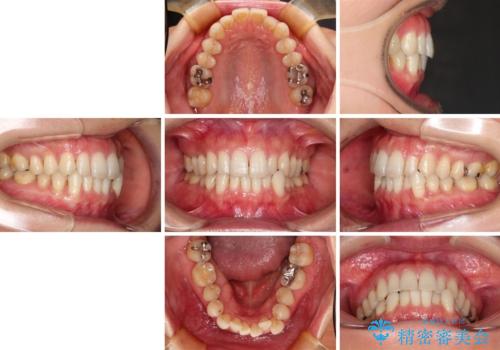

- 下顎の八重歯と、上下のクロスバイトを気にして来院された患者様です。

インビザラインを用い、下顎全体の後方移動、IPR(歯と歯の間を削る)と歯列全体を拡大させることで、歯並びを整えていくこととしました。

奥に位置していた上の前歯が下の前歯を乗り越える際、奥歯でものを咬むことができず、辛い時期が続きました。